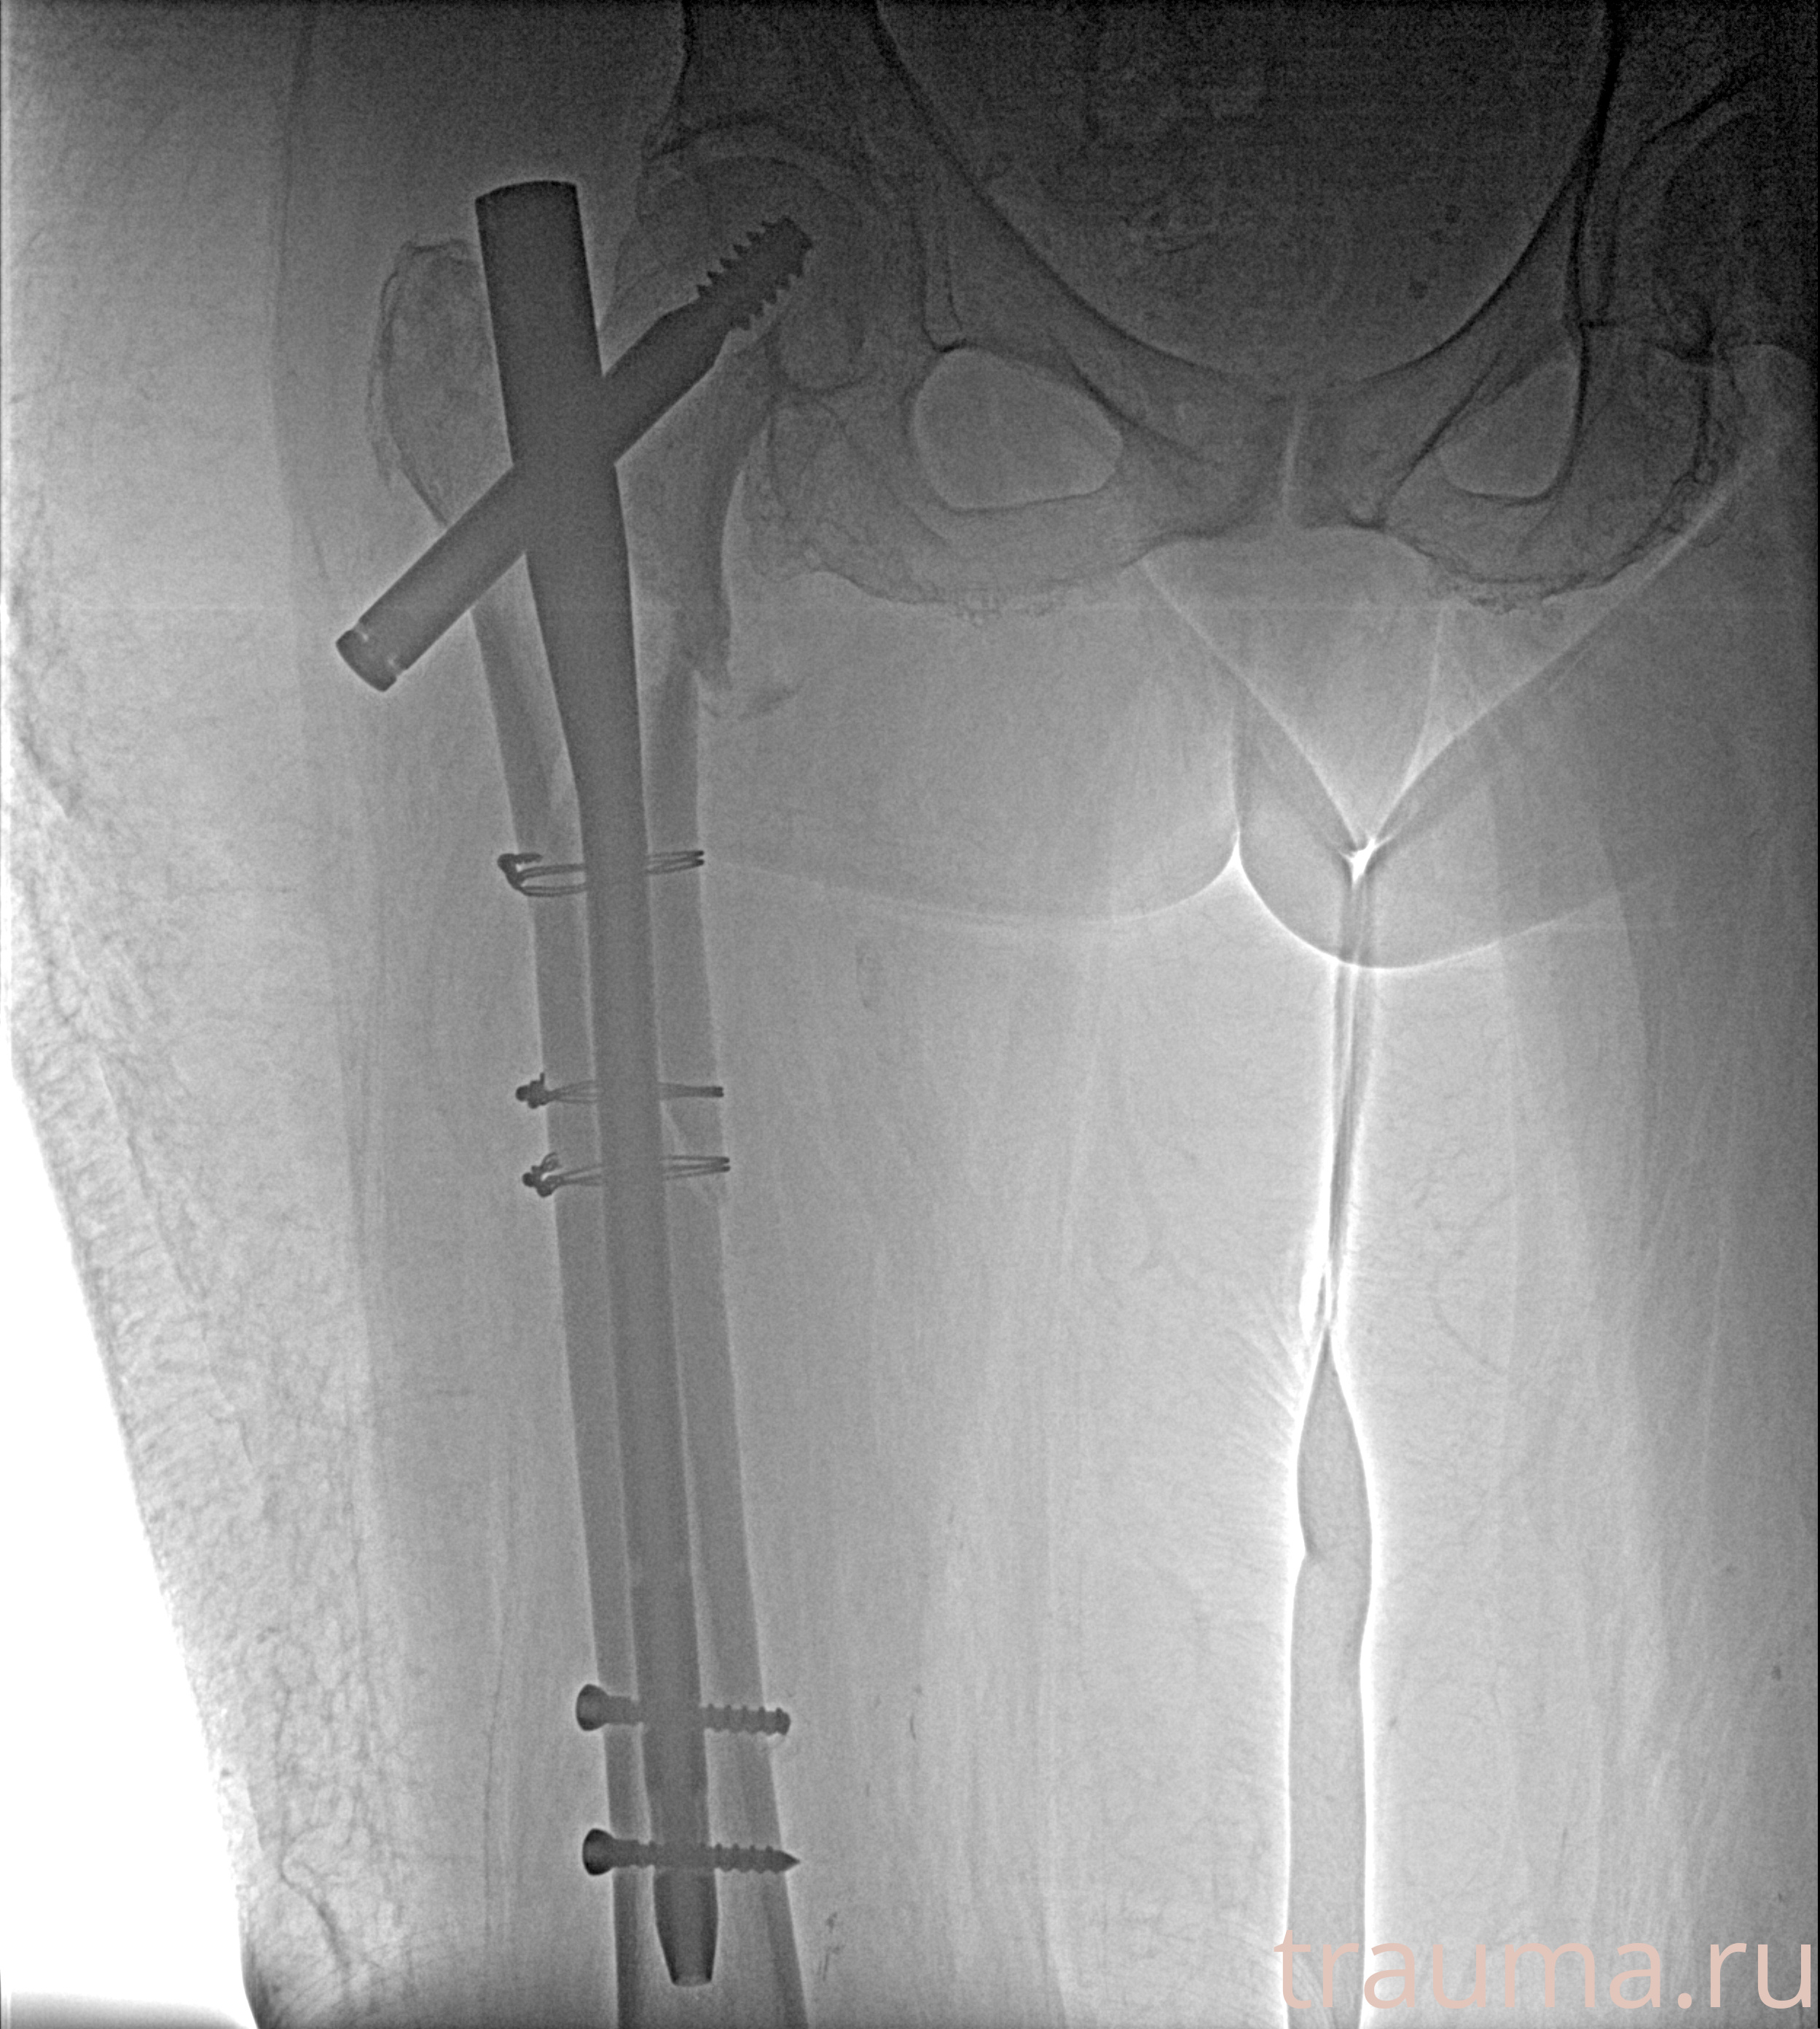

Рентгенограммы

Рентген на дому: по вашему адресу приезжает врач-рентгенолог, травматолог-ортопед с мобильным рентгеновским аппаратом, проводит диагностику травмы или заболевания, делает необходимые рентгенограммы, дает рекомендации по дальнейшему лечению. Получить качественные снимки в домашних условиях возможно благодаря уникальной методике, разработанной МосРентген Центром для института  Склифосовского